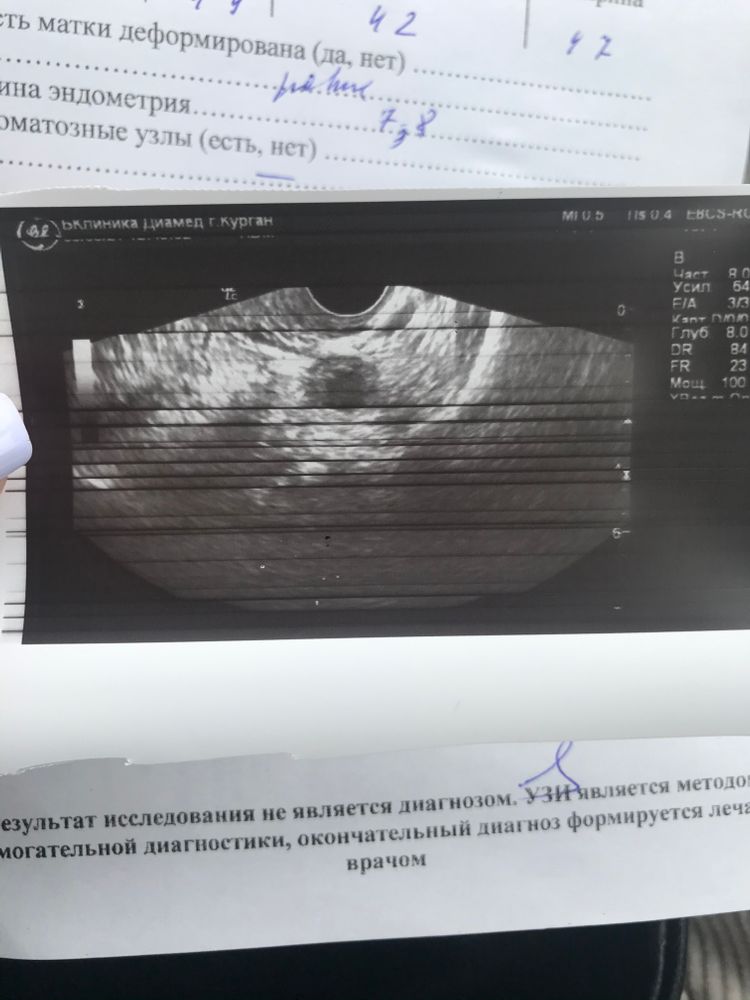

и вот ее заключение. Говорит что овуляцию была,

-эндометрий хороший 8

-жидкость есть

-овуляция была в правом яичнике( там у меня и болело

Прикрепляю заключение и снимок